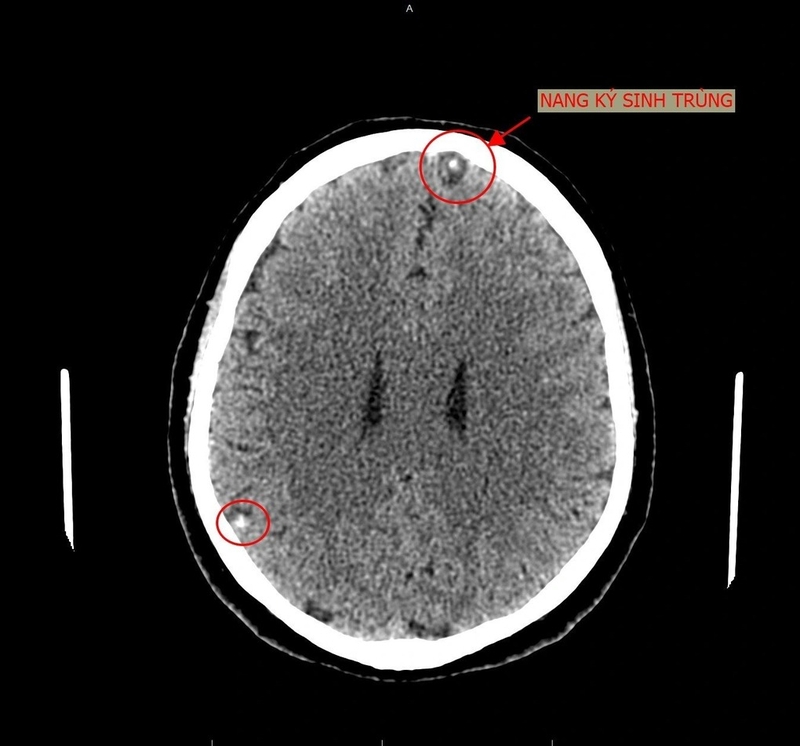

Nhiễm ký sinh trùng não gây ra một vấn đề nghiêm trọng cho sức khỏe con người. Chỉ khi phát hiện sớm mới có thể tránh được những hậu quả nguy hiểm. Hãy cùng tìm hiểu về nguyên nhân, triệu chứng và cách phòng ngừa nhiễm ký sinh trùng não qua bài viết dưới đây.

Nhiễm ký sinh trùng có thể dẫn đến nhiều biến chứng nguy hiểm trong đó có nhiễm ký sinh trùng não. Vì khi ký sinh trùng tấn công và đã xâm nhập được vào cơ thể, người bệnh không phát hiện kịp thời, ký sinh trùng sẽ di chuyển đến nhiều vị trí khác trong cơ thể. Từ đó, dẫn đến nhiều hậu quả nghiêm trọng như viêm màng não, viêm phổi, viêm ruột, tắc ống mật, tắc ruột,... Nhất là với người bệnh đang có tình trạng suy giảm miễn dịch thì biến chứng ký sinh trùng để lại càng nặng nề hơn.

Nhiễm ký sinh trùng não thường gặp ở giun đũa chó, giun mạch, sán máng, sán lá phổi, giun đầu gai,... dẫn đến viêm màng não do ký sinh trùng và nhiều triệu chứng như đau đầu, đau vùng thùy thái dương, thùy chẩm, đau nhức mỏi phần cổ và gáy, thị lực suy giảm,...